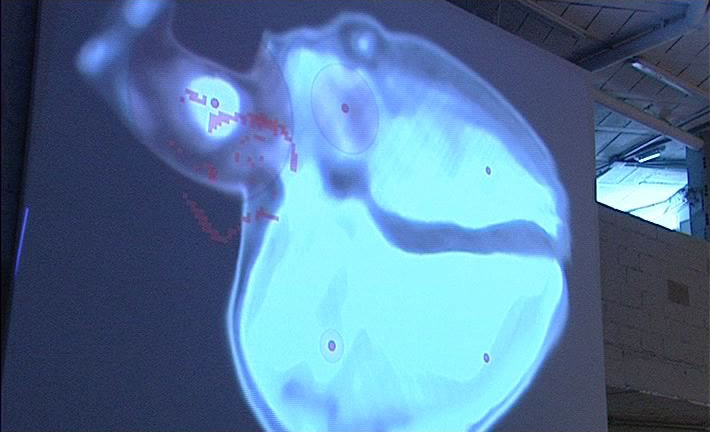

Dentro del espacio expositivo se instaló una superficie de proyecion de 4x5m en la cual se proyecta autentica imagen del corazón de la artista, realizada en cooperación con el equipo médico del hospital y el equipo técnico de rodaje.

En el suelo del mismo espacio expositivo se encuentra una representación esquemática de la sección transversal del corazón con la exacta nomenclatura latina de sus partes.

El acercamiento del visitante a cierta área del mismo esquema inicia un concreto autentico sonido, que se produce en esa parte del órgano. Al mismo tiempo, la superficie de proyección muestra las figuras pixeladas de los participantes y su movimiento en partes del corazón proyectado. El visitante, como el receptor básico y a la vez el factor de cambio, al moverse dentro de la sección esquemática del corazón provoca cambios visuales y acústicos.